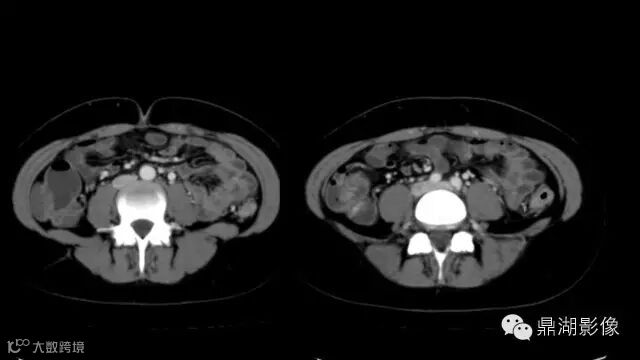

do you know comb sign?

The comb sign refers to the hypervascular appearance of the mesentery in active Crohn disease.

what's the meaning of fat halo sign?

粘膜下水肿或脂肪沉积,可致肠壁内呈低密度层(halo征),其最初用来描述溃疡性结肠炎,是良性肠道病变的结果,无特异性,也可存在于放射性肠炎,移植-受体疾病和慢性缺血性肠炎以及单性的肥胖症患者。

Fat halo aslo can be seen in normal terminal ileum.

It is the comb sign the most specific sign for crohn's disease.